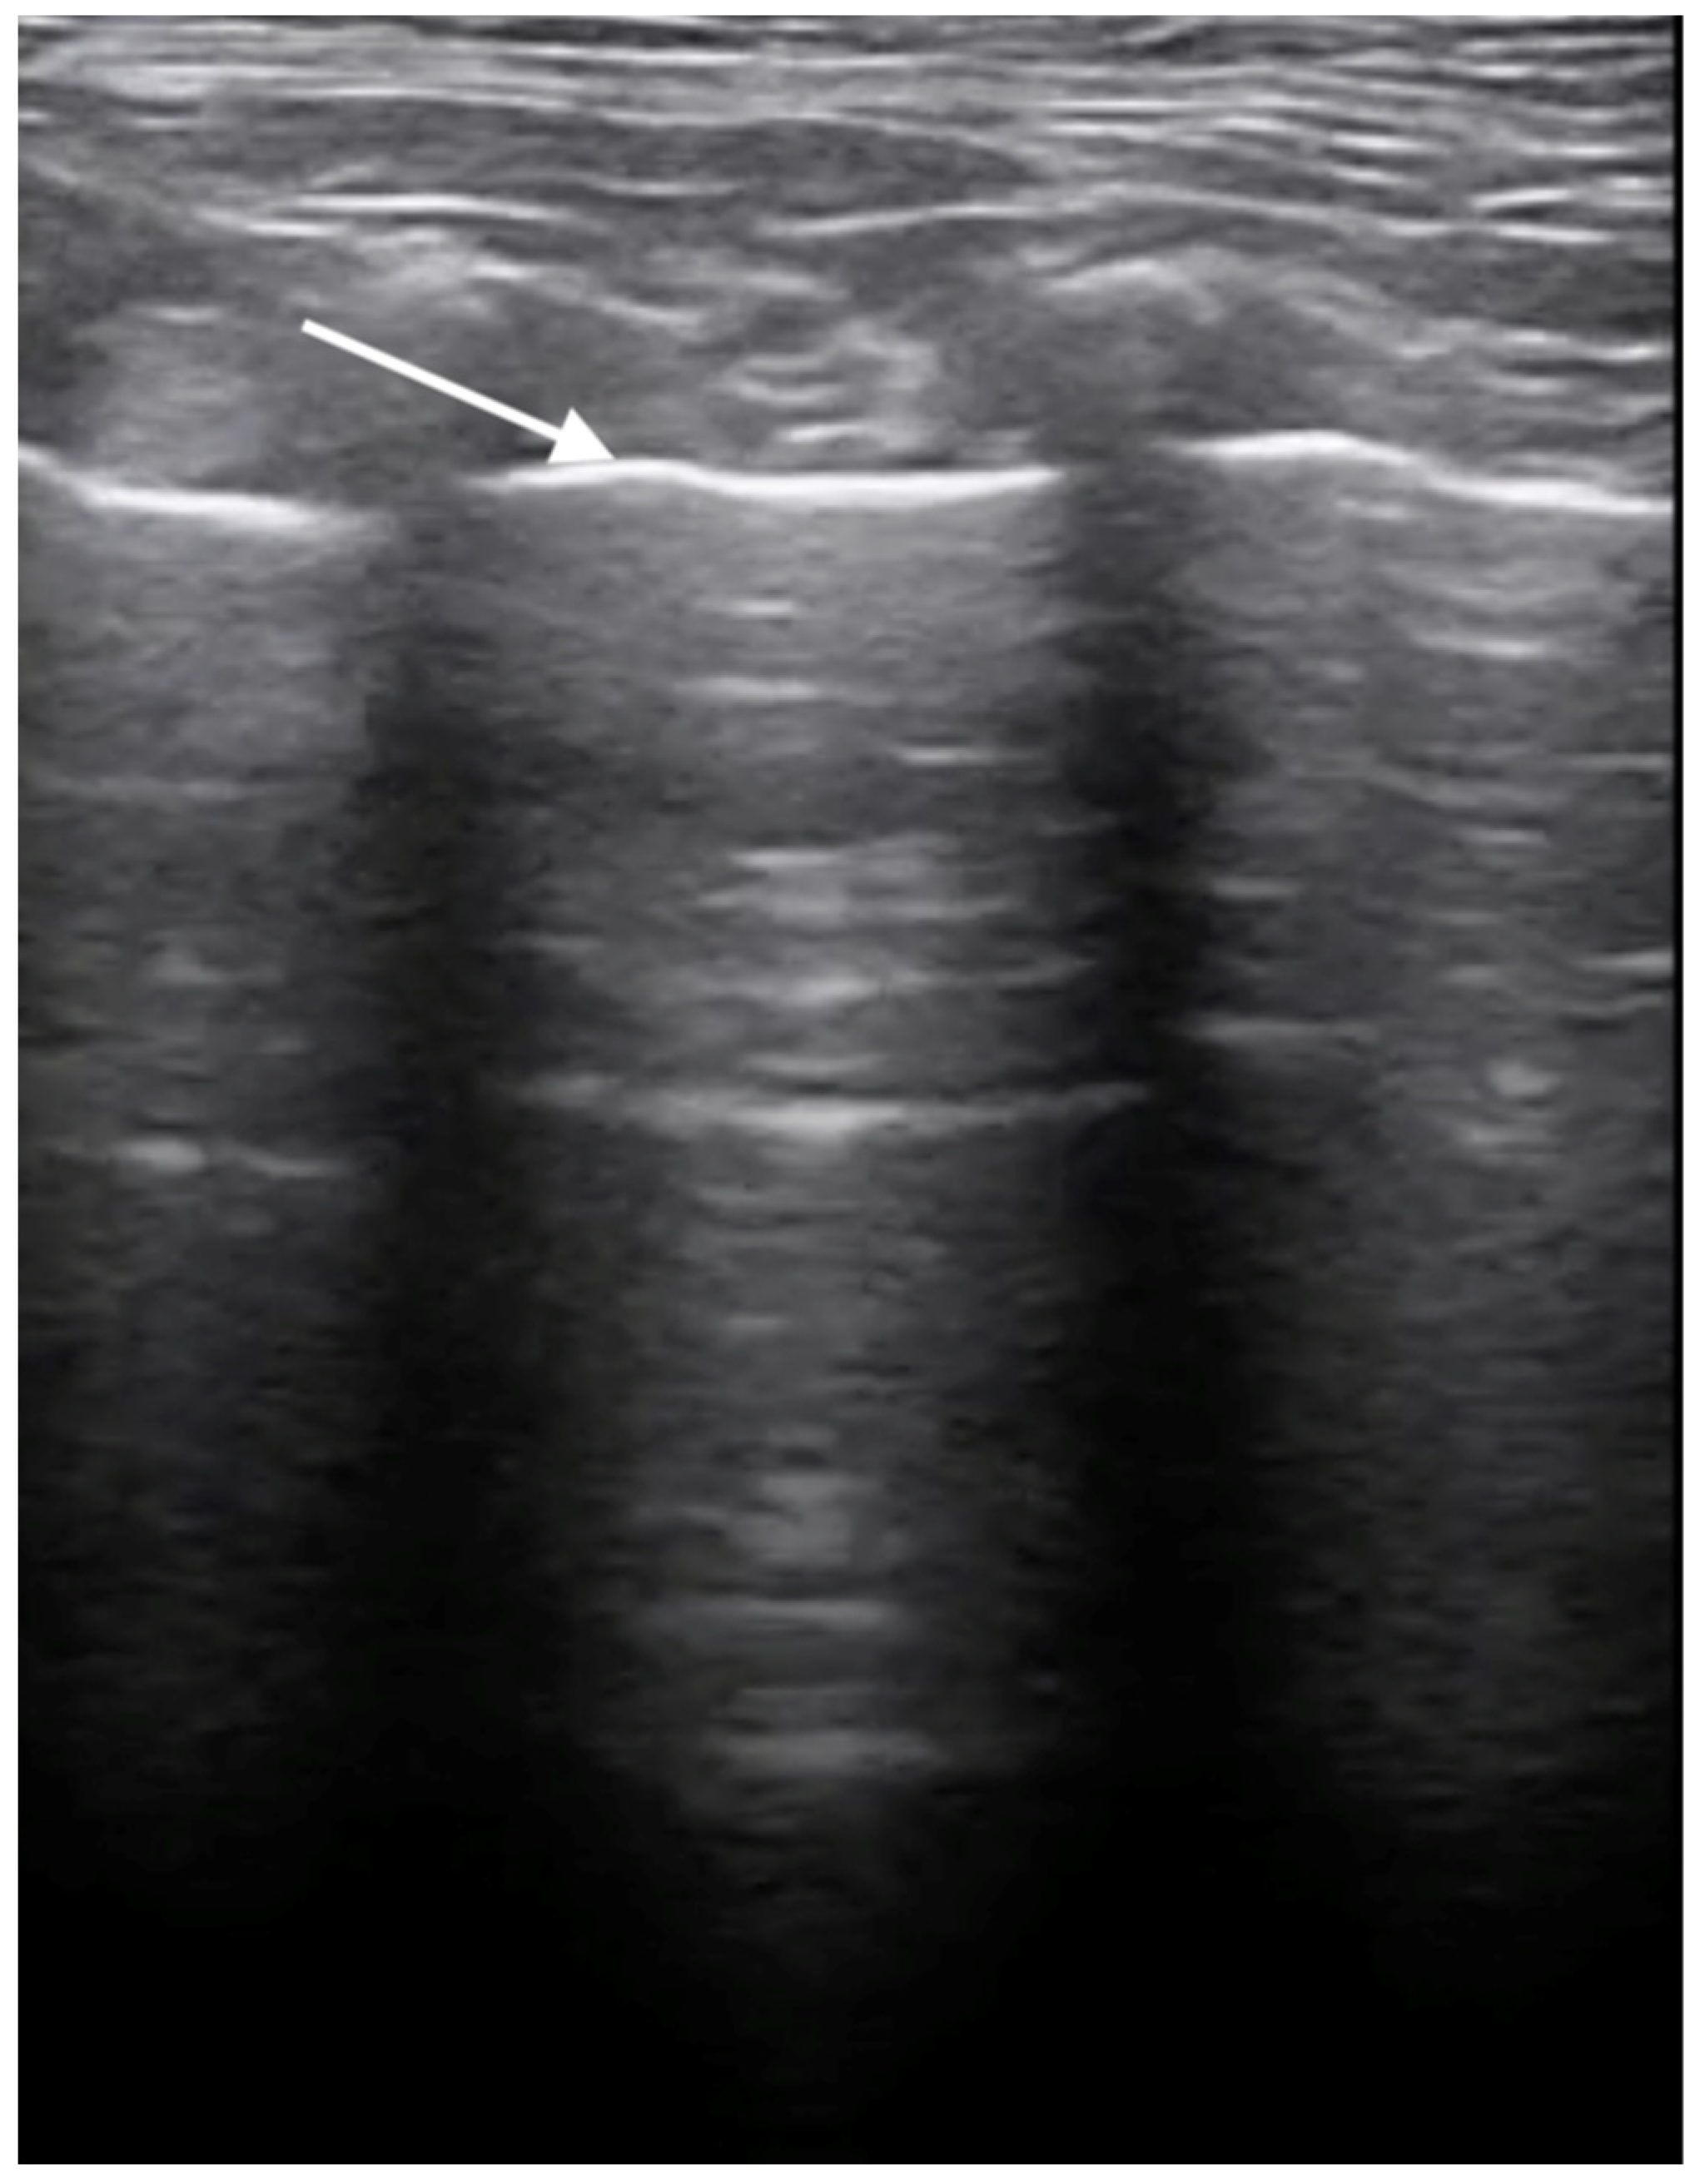

3.3. X-ray and Ultrasound Examination

No pathological changes were detected in the lung parenchyma image in the X-ray (Figure 1 and Figure 2). The ultrasound examination revealed in all views a normal, aerated lung pattern. The pleural line was intact, and A-line artifacts were present (Figure 3). The sliding sign was also observed. Echocardiography revealed a mild thickening of the mitral valve leaflets and a slight regurgitation (Figure 4) of this valve. The size of the heart chambers was within the normal range, and myocardial contractility was normal.

Figure 3.

Ultrasonographic examination of the lungs. Image of a healthy lung filled with air; the white arrow indicates the normal, smooth pleural line.